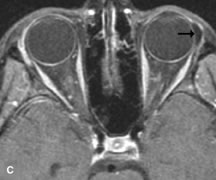

On MRI, uveal melanomas have a typical appearance that helps to differentiate them from other primary and secondary intraocular tumors as well as choroidal detachments. Pigmented melanomas are hyperintense on Tl-weighted images, hypointense on T2-weighted studies, and hyperintense on proton density–weighted examinations (Fig. 24).30,31,50,80–82 These signal characteristics have been attributed to the paramagnetic properties of melanin because of stable free radicals that shorten the T1 and T2 relaxation times. Moderate enhancement is seen on postgadolinium T2-weighted images. Gadolinium-enhanced T1-weighted images are particularly sensitive in detecting choroidal melanomas.83 MRI may be less sensitive in detecting extrascleral extension of tumor than echography performed by an experienced ultrasonographer.84

Fig. 24. A. T1- and (B) T2-weighted MR scans demonstrate a small nodular intraocular mass (arrows) that is very hyperintense on the T1-weighted scan and hypointense on the T2-weighted image. This signal intensity pattern is due to the presence of free radicals within melanin granules. C and D. Postcontrast fat-suppressed T1-weighted scans demonstrate homogeneous intense enhancement of the lesion and no evidence of seleral penetration or optic nerve invasion.